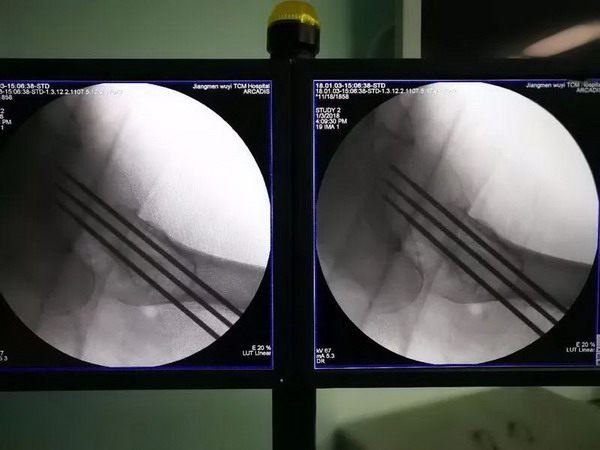

蓝阿姨摔了一跤后,她的右侧股骨颈出现骨折,在江门市五邑中医院治疗。经过会诊,医院医疗团队决定为蓝阿姨实施闭合复位空心螺钉内固定术,不过与以往不同的是,这次使用机器人辅助实施手术。

传统骨科手术是专科医生通过X光射线透视“看到骨头”进行定位,这种定位方式缺少立体空间,仅凭借“一双肉眼”难免出现“分厘偏差”,手术操作困难,且风险较高。

现在使用“天玑”骨科手术机器人,术中先利用C臂X光机对手术部位进行拍摄标记,然后将图像传送到计算机上,并进行置钉位置规划,然后利用导航技术,类似GPS一样,引导机械臂到指定位置。这样,医生就可以在机器人的辅助下准确置入内固定,可精确到0.8mm以内,真正实现“毫厘不差”,让手术更完美。

在骨科机器人的协助下,这台手术时间短,手术创伤很小,手术切口约1厘米,而且没有什么出血。简单来说,就是精准、微创、耗时少。这是我市首例机器人辅助骨折固定术,也标志着我市骨科手术正式迈入了智能化、精准化、微创化的机器人手术新时代。

“机器人的成功应用,使我们的手术操作简单了。机器人规划精准路径,把手术难点解决了。我们只要把螺钉打进去就可以,由于精准度更高,大大降低了医疗风险,患者更有安全感。”区文欢主任说。

目前,江门市五邑中医院在机器人应用方面主要应用在股骨颈骨折空心钉内固定、骨盆骨折空心钉内固定以及脊柱椎弓根置钉等。就拿股骨颈骨折来说,准确的置钉可以使到股骨颈骨折端均匀加压,骨折端更稳定,有利于骨折的愈合和减少股骨头坏死的风险。